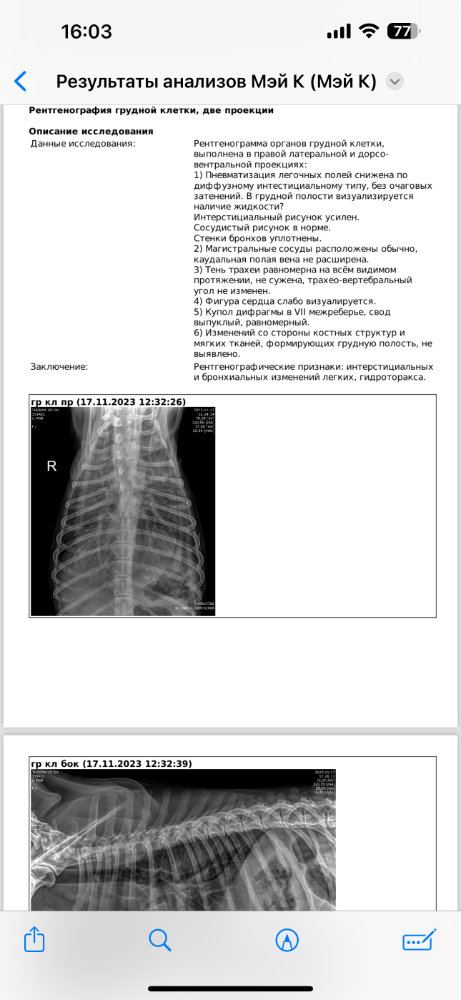

Mosfilmka & Remy Опубликовано 17 ноября, 2023 Автор Опубликовано 17 ноября, 2023 Прошли рентген, сделали узи, увидели небольшой асцит. Ждёт вердикт терапевта, что будем делать

Mosfilmka & Remy Опубликовано 17 ноября, 2023 Автор Опубликовано 17 ноября, 2023 Обнаружили вторичный шунт в печени, в грудной клетке тоже жидкость, от этого и кашляет (( надо откачать, чтобы дышалось нормально очень прошу помощи!! Чек уже на 21 тыс в клинике, еще 5600 было шанс био

Mosfilmka & Remy Опубликовано 17 ноября, 2023 Автор Опубликовано 17 ноября, 2023 Биоконтроль перепроверил шанс био по альбумину и белку. не удалось откачать жидкость из грудной полости без седации, не дается ребенок. Везде смирно лежала, а здесь именно нет и все. прописали верошпирон… консультируюсь с Алексеевой, все ли верно… назначали гептрал, Апоквел, верошпирон и далее по списку…